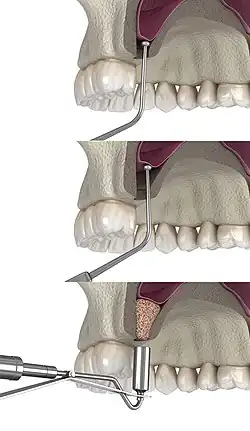

2) The soft tissue is flapped back to expose the underlying lateral wall of the left maxillary sinus.

3) The bone has been removed with a piezoelectric instrument, exposing the underlying Schneiderian membrane, which is the lining of the maxillary sinus cavity.

4) Through careful instrumentation, the membrane is peeled from the inner aspect of the sinus cavity.

5) The membrane has been reflected from the internal aspect of the inferior portion of the sinus cavity; one can now visualize the bony floor of the sinus cavity without its lining membrane (note the triangular ridge of bone within the sinus, known as an Underwood's septum).

6) The newly formed space within the bony cavity of the sinus, yet inferior to the intact membrane, is grafted with human cadaver allograft bone. The floor of the sinus will now be roughly 10mm or larger than before, providing enough room to place dental implants into the edentulous site.

The procedure is performed intraorally, where the surgeon makes an incision into the gum. Once the incision is made, the surgeon then pulls back the gum tissue, exposing the lateral bony wall of the sinus. The surgeon then creates a "window" into the sinus, exposing the Schneiderian membrane. The membrane is separated from the bone, and bone graft material is placed into the newly created space. The gums are then sutured closed, and the graft is left to heal for 4 to 12 months.[8]